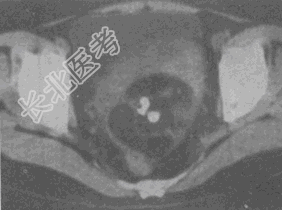

- 单项选择题女,52岁, 下腹部胀痛,B超提示盆腔占位, CT扫描如图所示,盆腔内见囊实性肿块, 其内CT值不均,从-120至300Hu不等, 最可能的诊断是

A、盆腔畸胎瘤

B、盆腔结核

C、子宫肌瘤

D、卵巢囊肿

E、卵巢黏液瘤